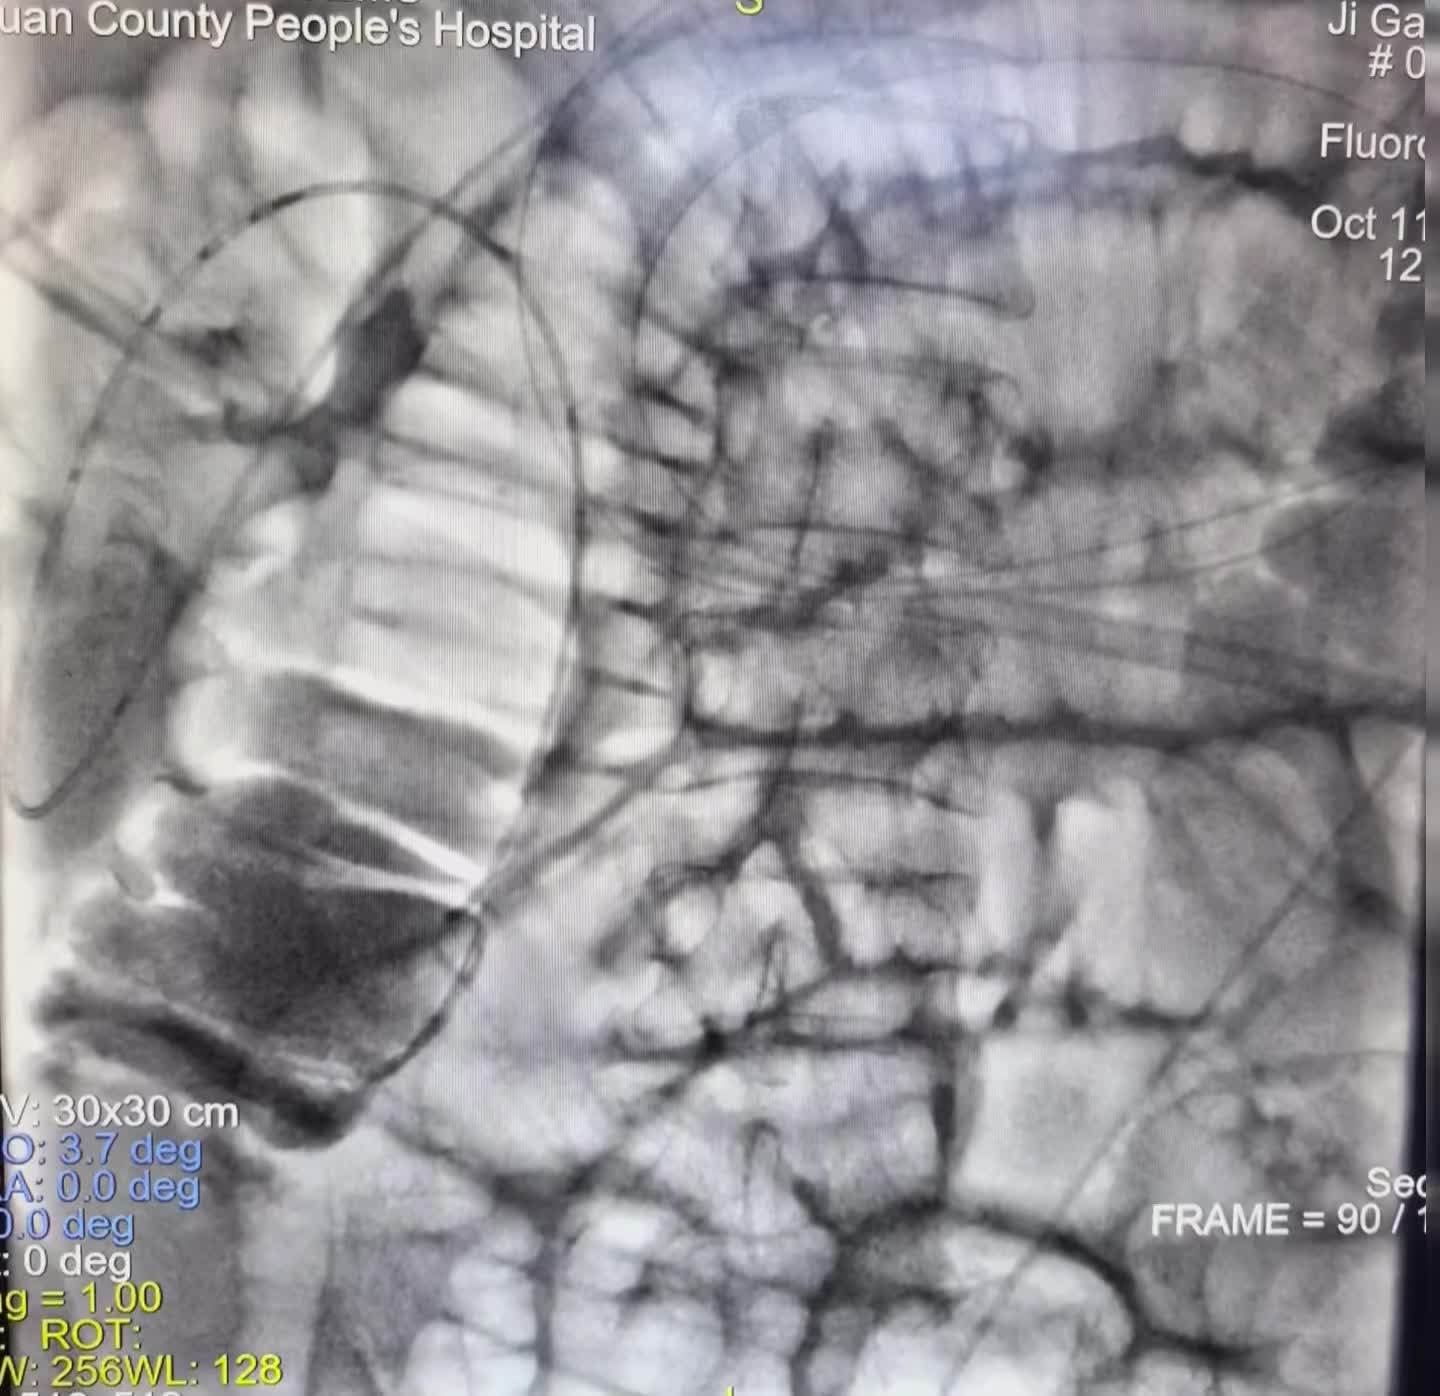

直肠癌术后3年,近期反复肠梗阻,胃管减压 直肠癌术后3年,近期反复肠梗阻,胃管减压1周,效果欠佳。今日在DSA可视化行肠管黏连松紧,及肠道减压管置入,直肠吻合狭窄扩张术,术后即可通便通气,腹胀,腹痛即可减轻。口。DSA可视化经鼻经肛双向开通,松解黏连介入治疗技术,安全有效,经自然腔道无创操做效果立竿见影。